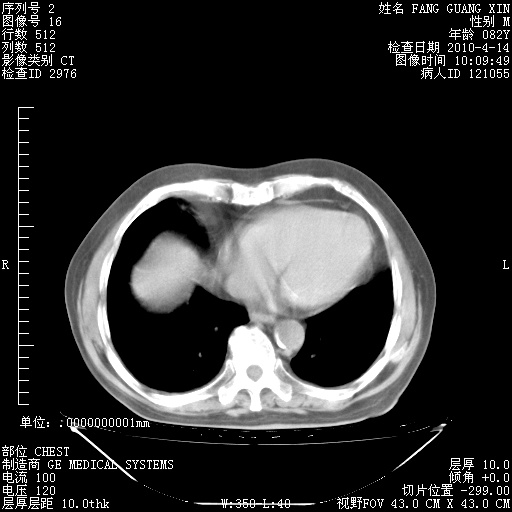

4月14日肺部CT

肺部CT平扫未见异常。

4月28日肺部CT——再次出现类似去年5月9日——透光度降低,(影像科认为)“间质性”改变。

4月28日肺部CT——再次出现类似去年5月9日——透光度降低,“间质性”改变。